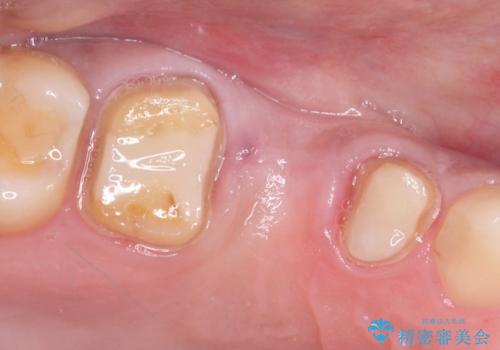

右上のブリッジが途中で切断されて、手前の歯が根の治療の途中でした。

根の治療を行いその後にオールセラミックブリッジを装着する計画となりました。